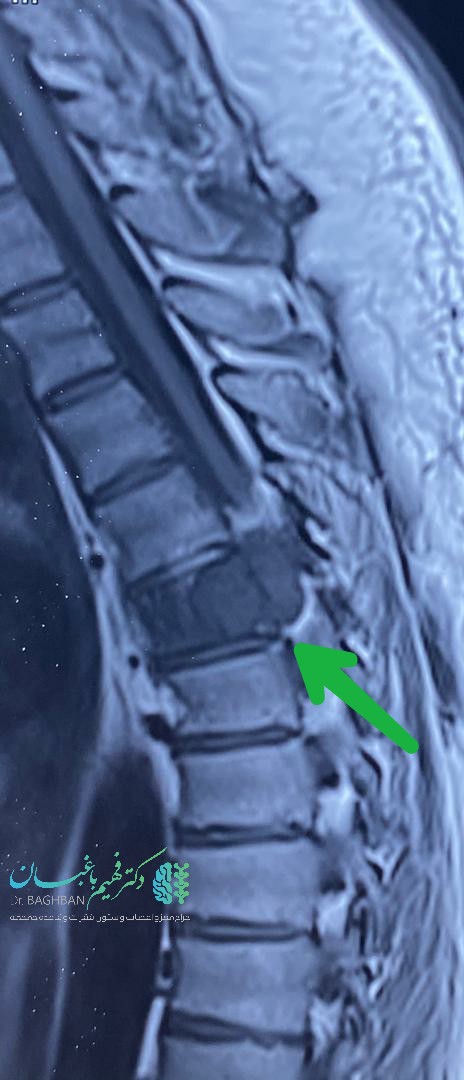

آقای میانسال با ضعف پیشرونده اندام های تحتانی و بی اختیاری ادرار و مدفوع مراجعه کرده بودند. تومور همانژیومای مهاجم مهره ششم توراسیک که سبب آسیب نخاع شده بود. بیمار با نورومانیترینگ دائمی تحت عمل جراحی قرار گرفتند که ابتدا نخاع آزاد و سپس کل مهره توسط سیمان ،ورتبروپلاستی شد. با تشکر از آقای دکتر حسین زاده، همکار محترم جراح اعصاب که عمل با یاری ایشان صورت گرفت.

تصاویر قبل و بعد ازعمل